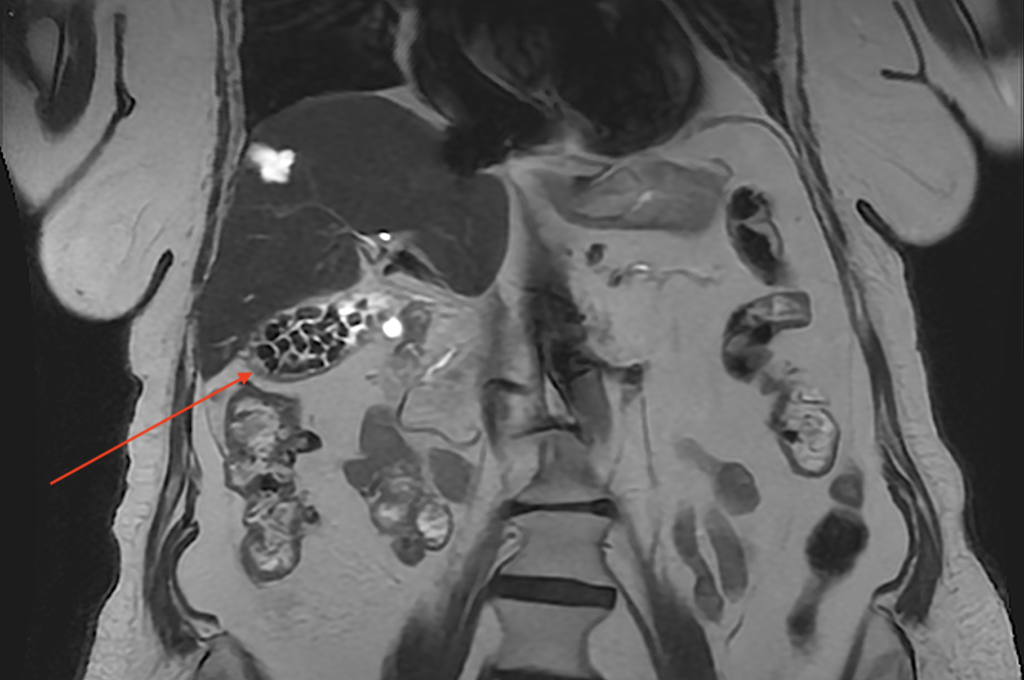

Σε κάποιες περιπτώσεις, οι πέτρες στη χολή είναι δυνατόν να καταστούν εμφανείς και στην μαγνητική τομογραφία άνω κοιλίας ή την MRCP (μαγνητική χολαγγειοπαγκρεατογραφία) που πραγματοποιούνται για άλλους λόγους.

Μαγνητική τομογραφία από γυναίκα ασθενή μας, η οποία αναδεικνύει πολυάριθμες πέτρες στη χολή που πληρούν το σύνολο της χοληδόχου κύστεως (βέλος).